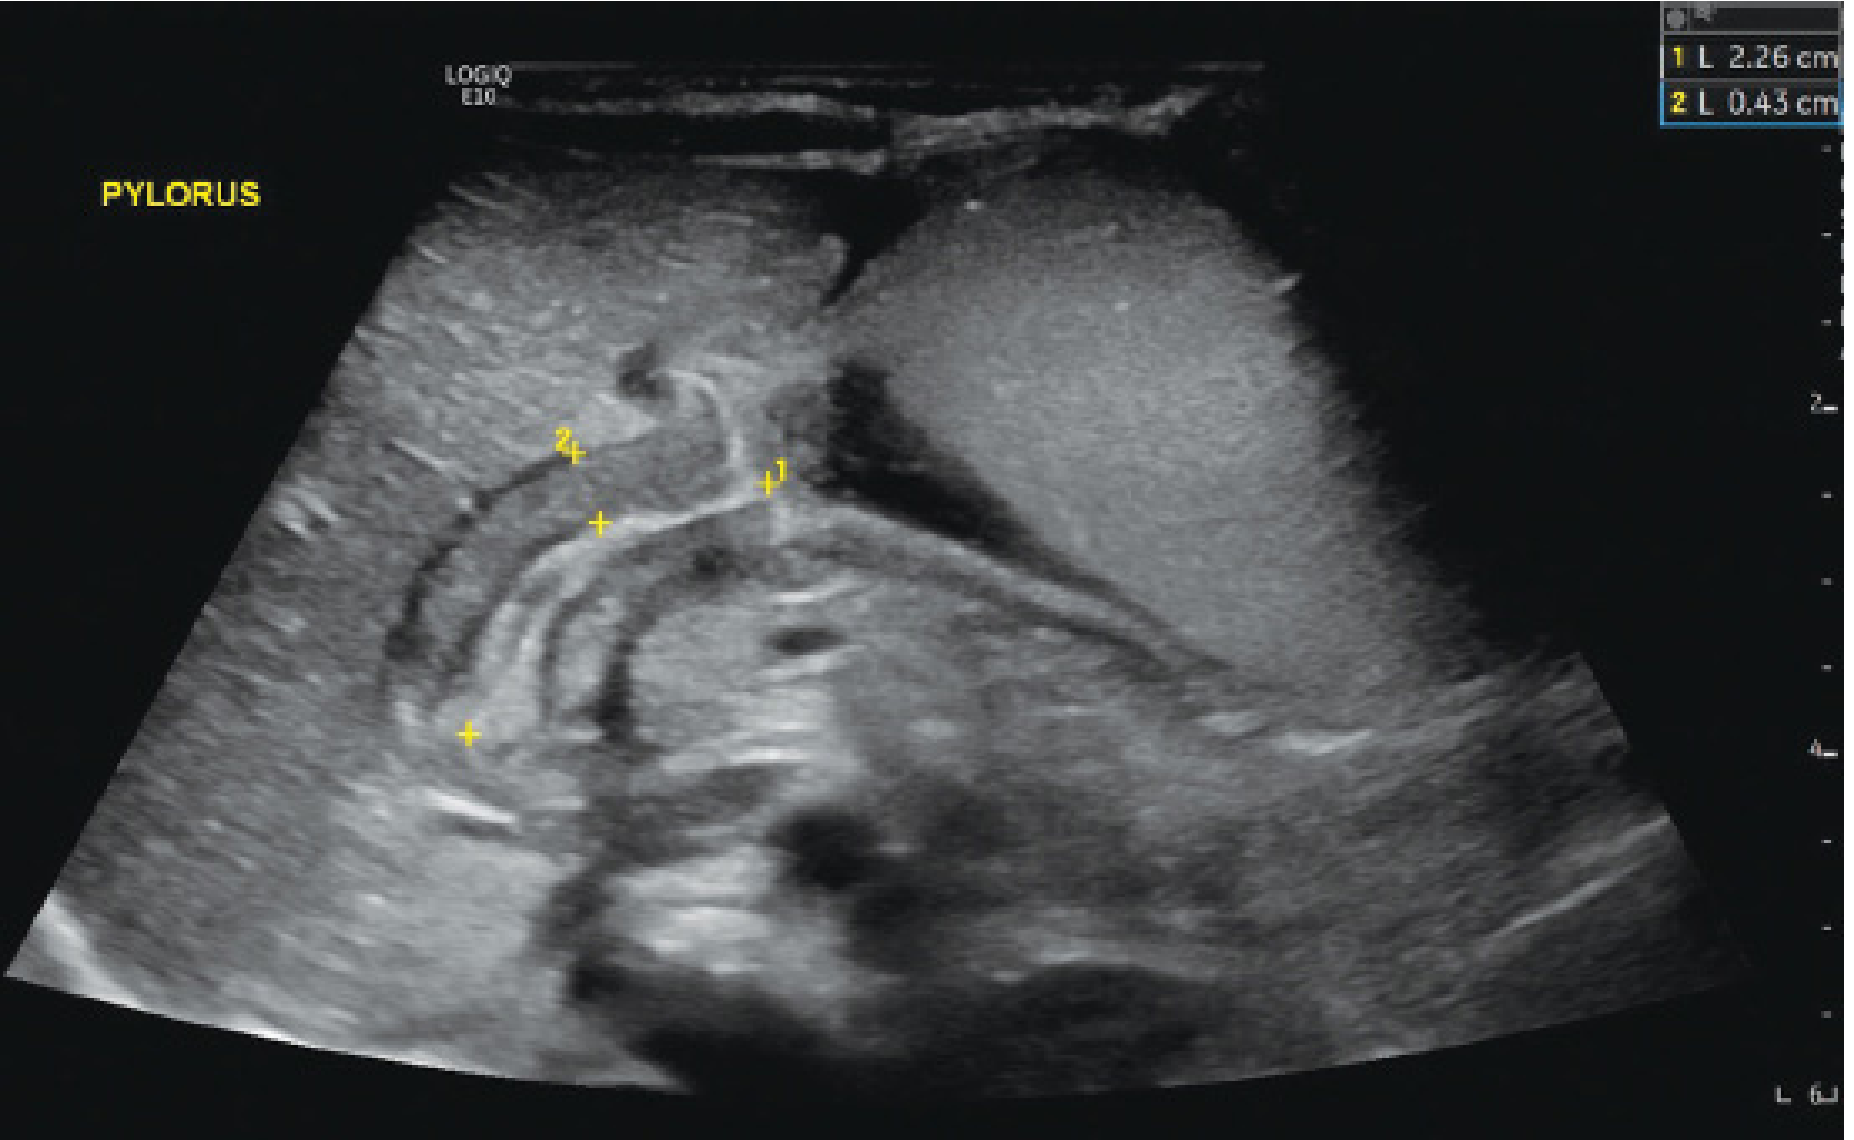

Ultrasound of pyloric stenosis

Ultrasound of pyloric stenosis in coronal plane with pyloric muscle marked by measurement bars — Mulholland and Greenfield's Surgery

Ultrasound (first-line):

• Pyloric muscle thickness ≥4 mm

• Pyloric channel length ≥15–19 mm

• Pyloric diameter >14 mm

• Sensitivity/specificity >95%